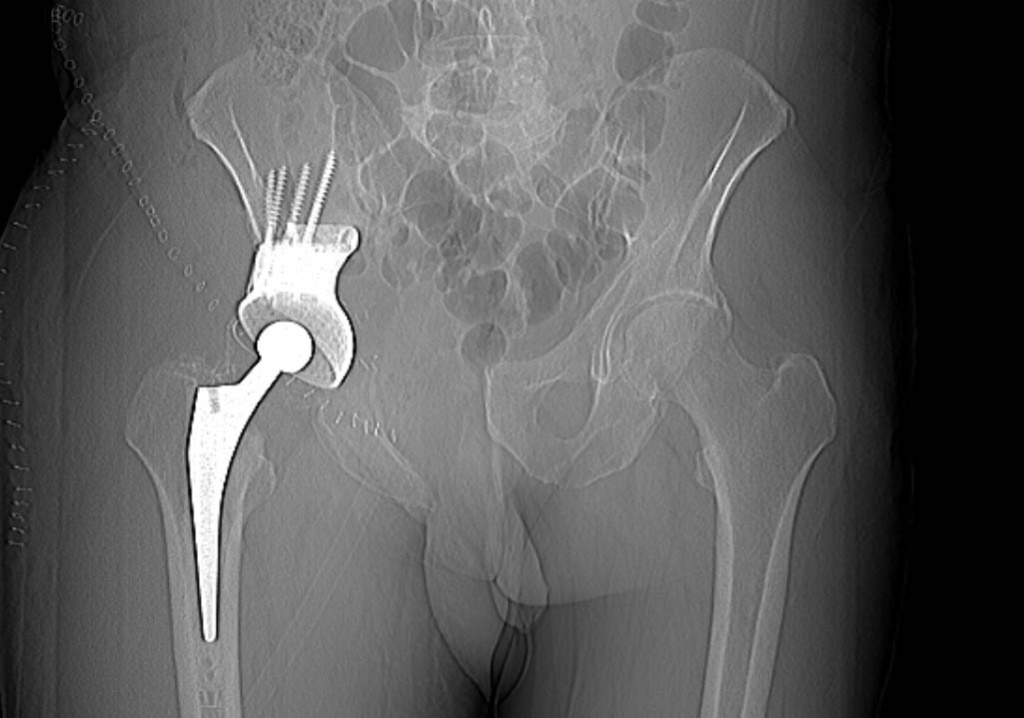

Следующий этап – операция. В первую очередь нужно рассматривать возможность проведения органосохраняющих вмешательств. Применение модульных систем эндопротезирования является самым актуальным и современным методом терапии костных сарком. Однако такой вид лечения должен проводиться только в специализированных крупных стационарах онкологического профиля, где есть команда онкоортопедов, собран опыт эндопротезирования при ЗНО костей, хорошо отработаны методики ревизионного эндопротезирования и есть специальное инновационное оборудование, а также высокотехнологичные хирургические инструменты.

В последние годы все более популярны 3D-принтинговые технологии. Это означает, что на основе данных, полученных от лучевой диагностики, выполняется 3D-моделирование операции и изготовление протеза индивидуально для каждого пациента.

Фото: Эндопротезирование при хондросаркоме тела подвздошной кости